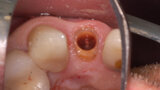

Fig. 12a: A post fracture presenting in the left central incisor, requiring extraction.

Fig. 12b: The occlusal view illustrated the cervical tissue volume and contours.